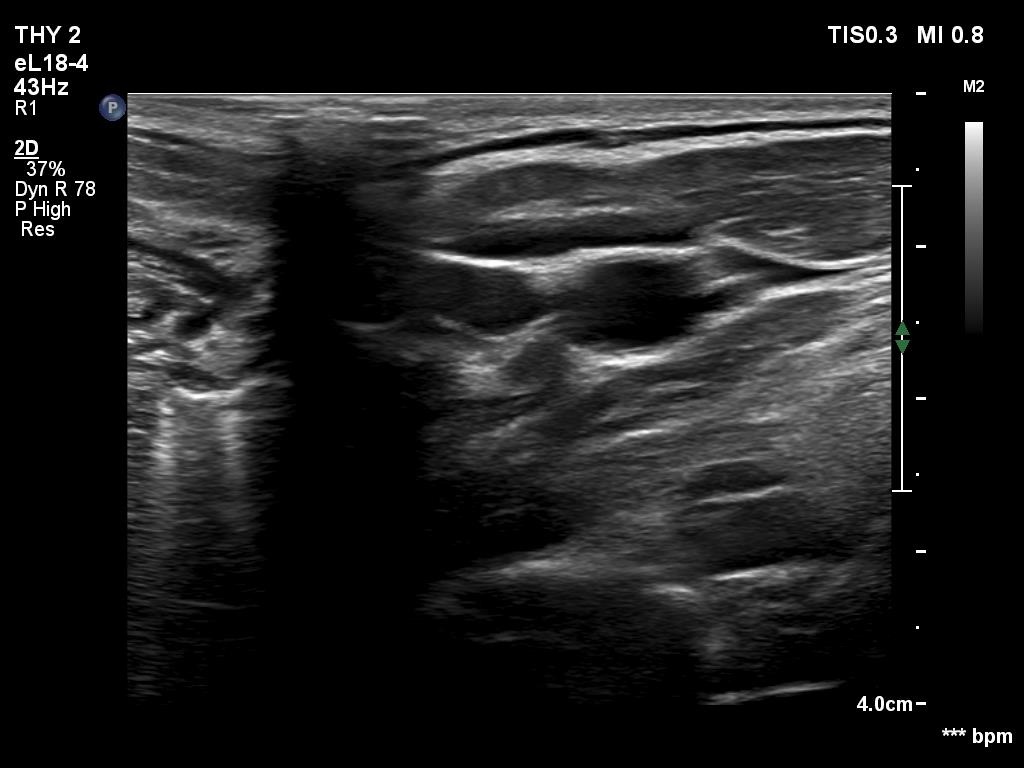

There was a hypoechoic mass with a regular hilum in the left submandibular area. The echo pattern was identical to the neighboring muscle fiber.

The differentiation of a lymph node from a discrete thickening of a muscle fiber can be challenging. If the node in this case would be non-palpable then it would be almost impossible to make this distinction. The echo patterns are identical and hilum-like adipose tissue is a common finding in muscle fibers. The only important ultrasound feature is the presence of vascularity according to the hilum. This was not demonstrated on color Doppler mode but was on microflow imaging.